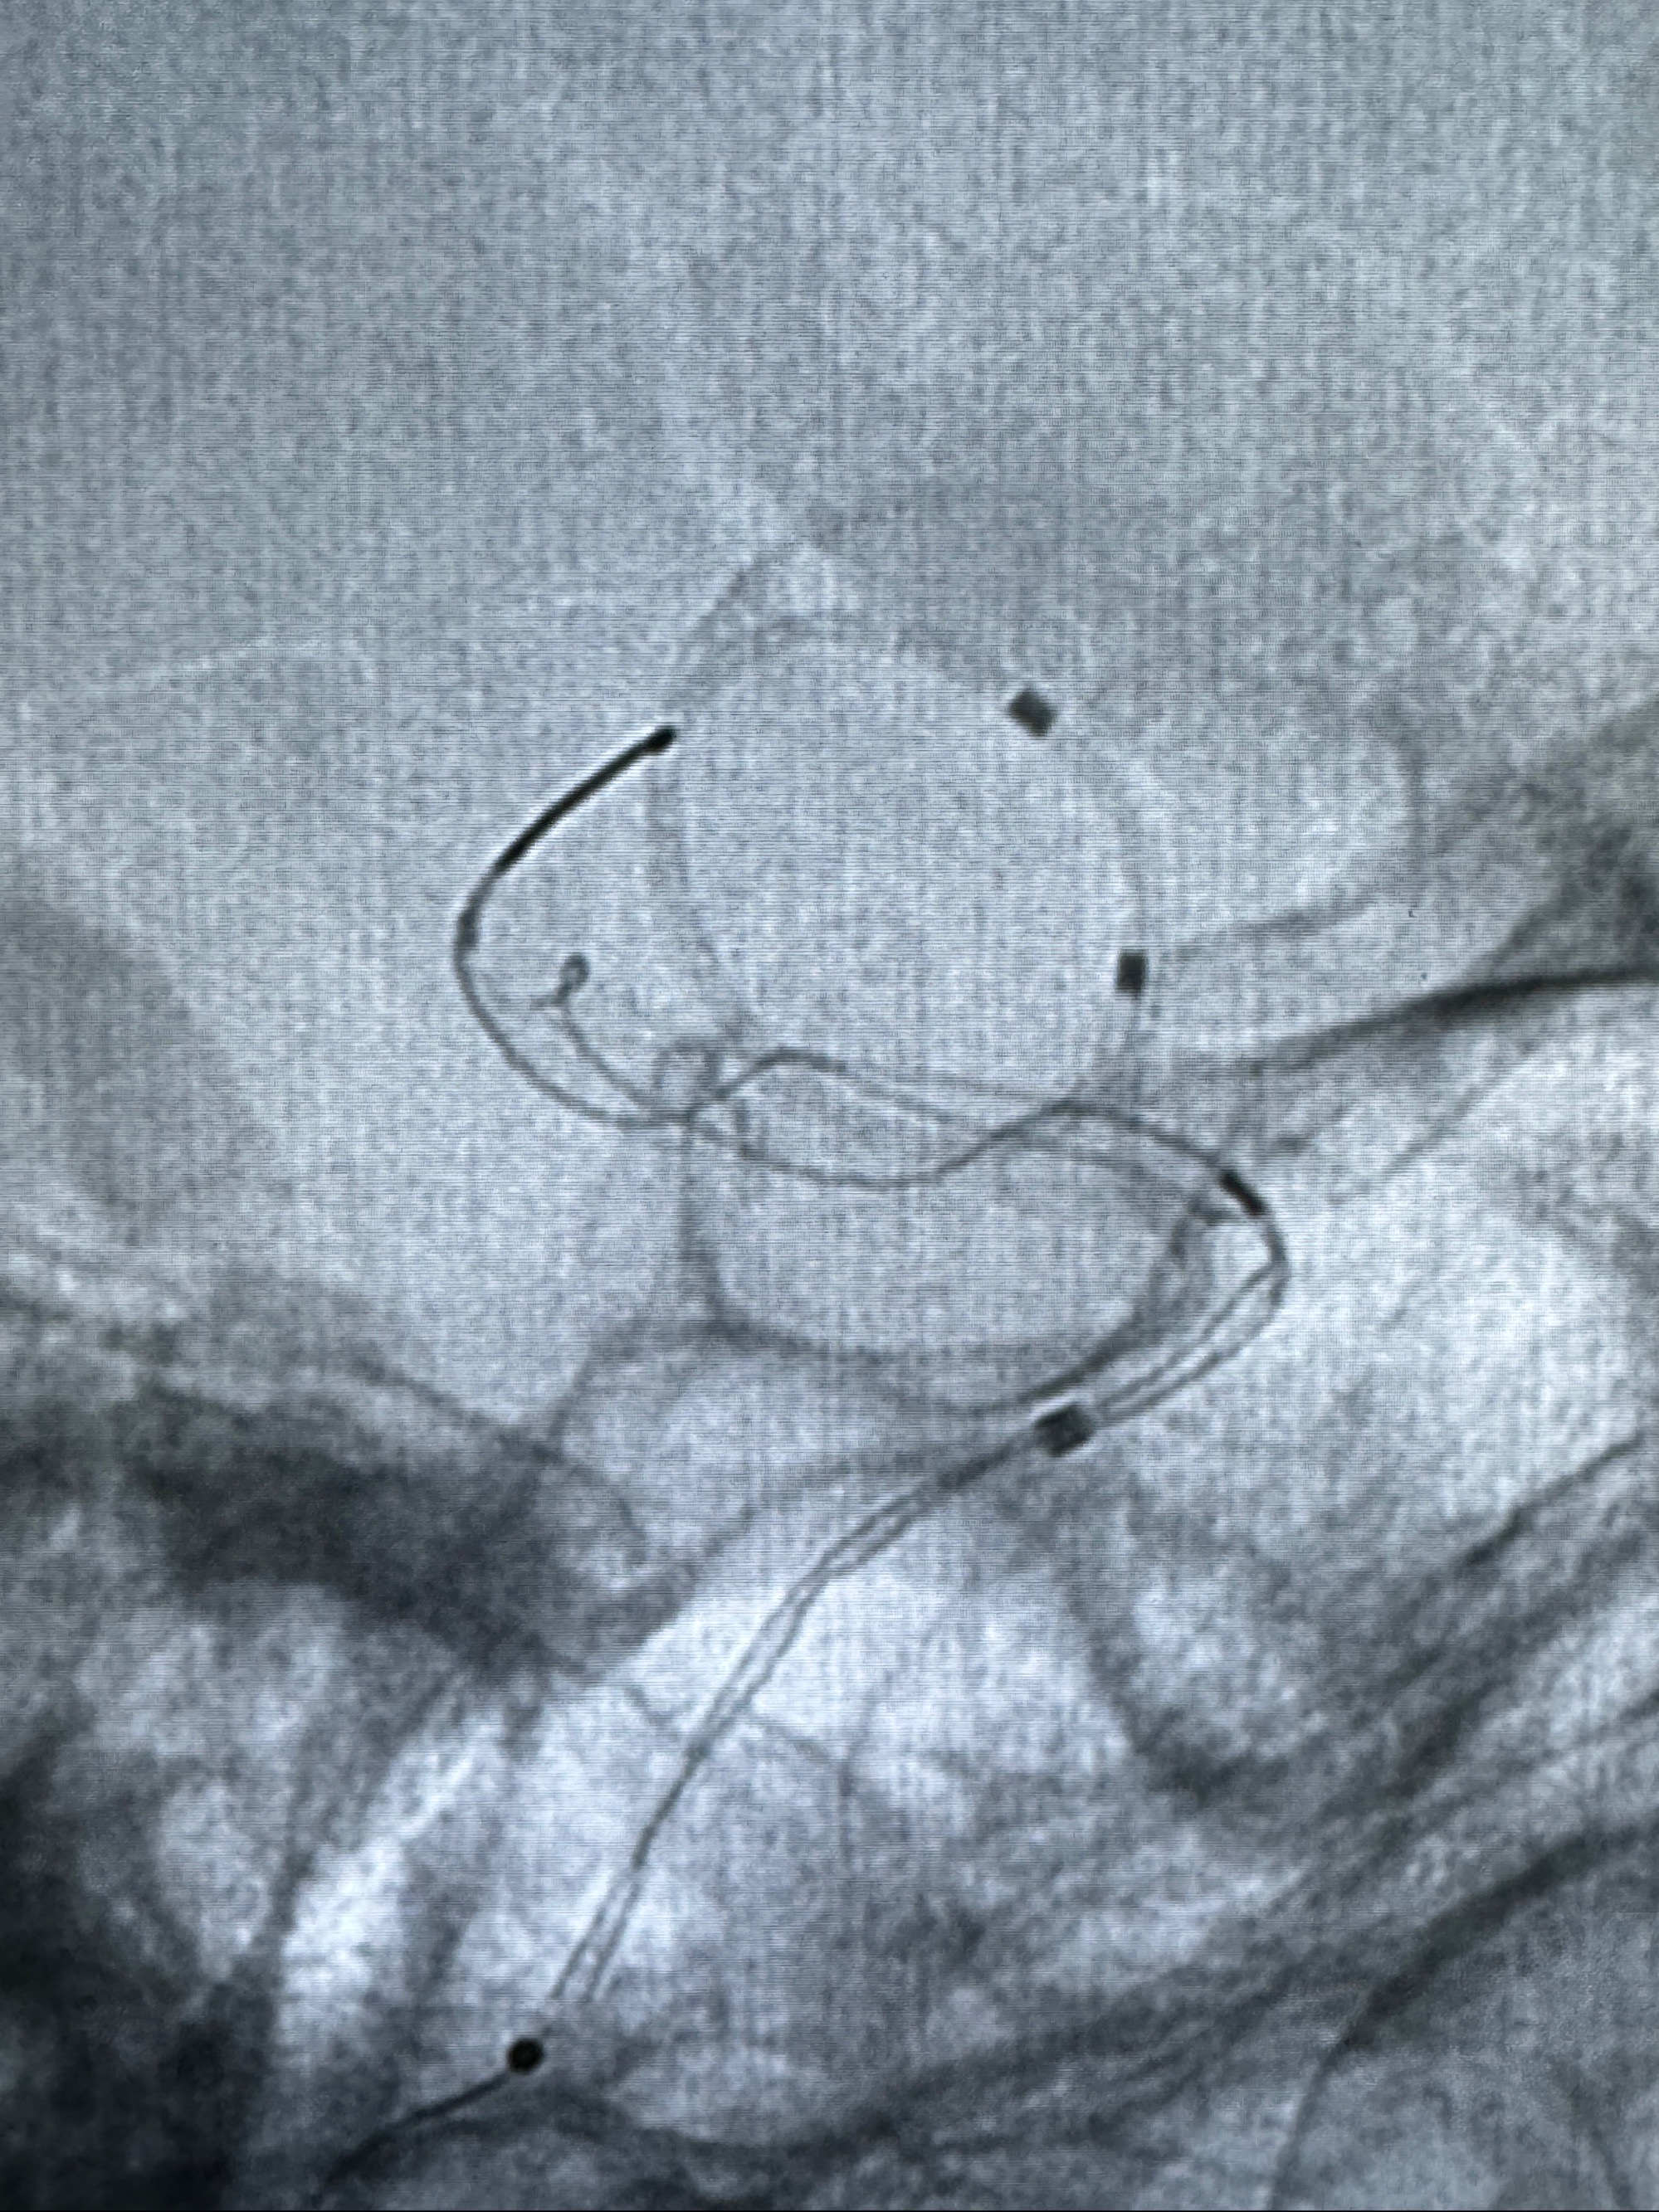

4.5-30mmTurbridge密网支架,于M1近心端打开

透视下支架释放满意

多角度显示支架打开情况

造影显示支架贴壁情况

调整好角度,透视下推挤支架,使支架贴壁

再次造影确认支架贴壁情况

预备完全释放支架